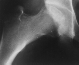

W.H.. 12-year-old-girl. Post-traumatic avascular necrosis of rt.

femoral head. She sustained the right femoral neck fracture by

falling from a balcony.

After bed-rest for 2 weeks, she started walking with crutches.

She completely returned to normal activities 6 months after the

trauma. She was beginning to complain of the right hip pain 2

years after the trauma. A large area of avascular necrosis was

in weight bearing surface of the femoral head.

The large posterior surface of the femoral head remained intact.

A Sugioka osteotomy was performed with 90 degrees of anterior

rotation and 15 degrees of varus angulation. After post-operative

non-weight-bearing for 4 weeks, and partial-weight-bearing for

6 weeks, she has had neither limping nor pain so far.